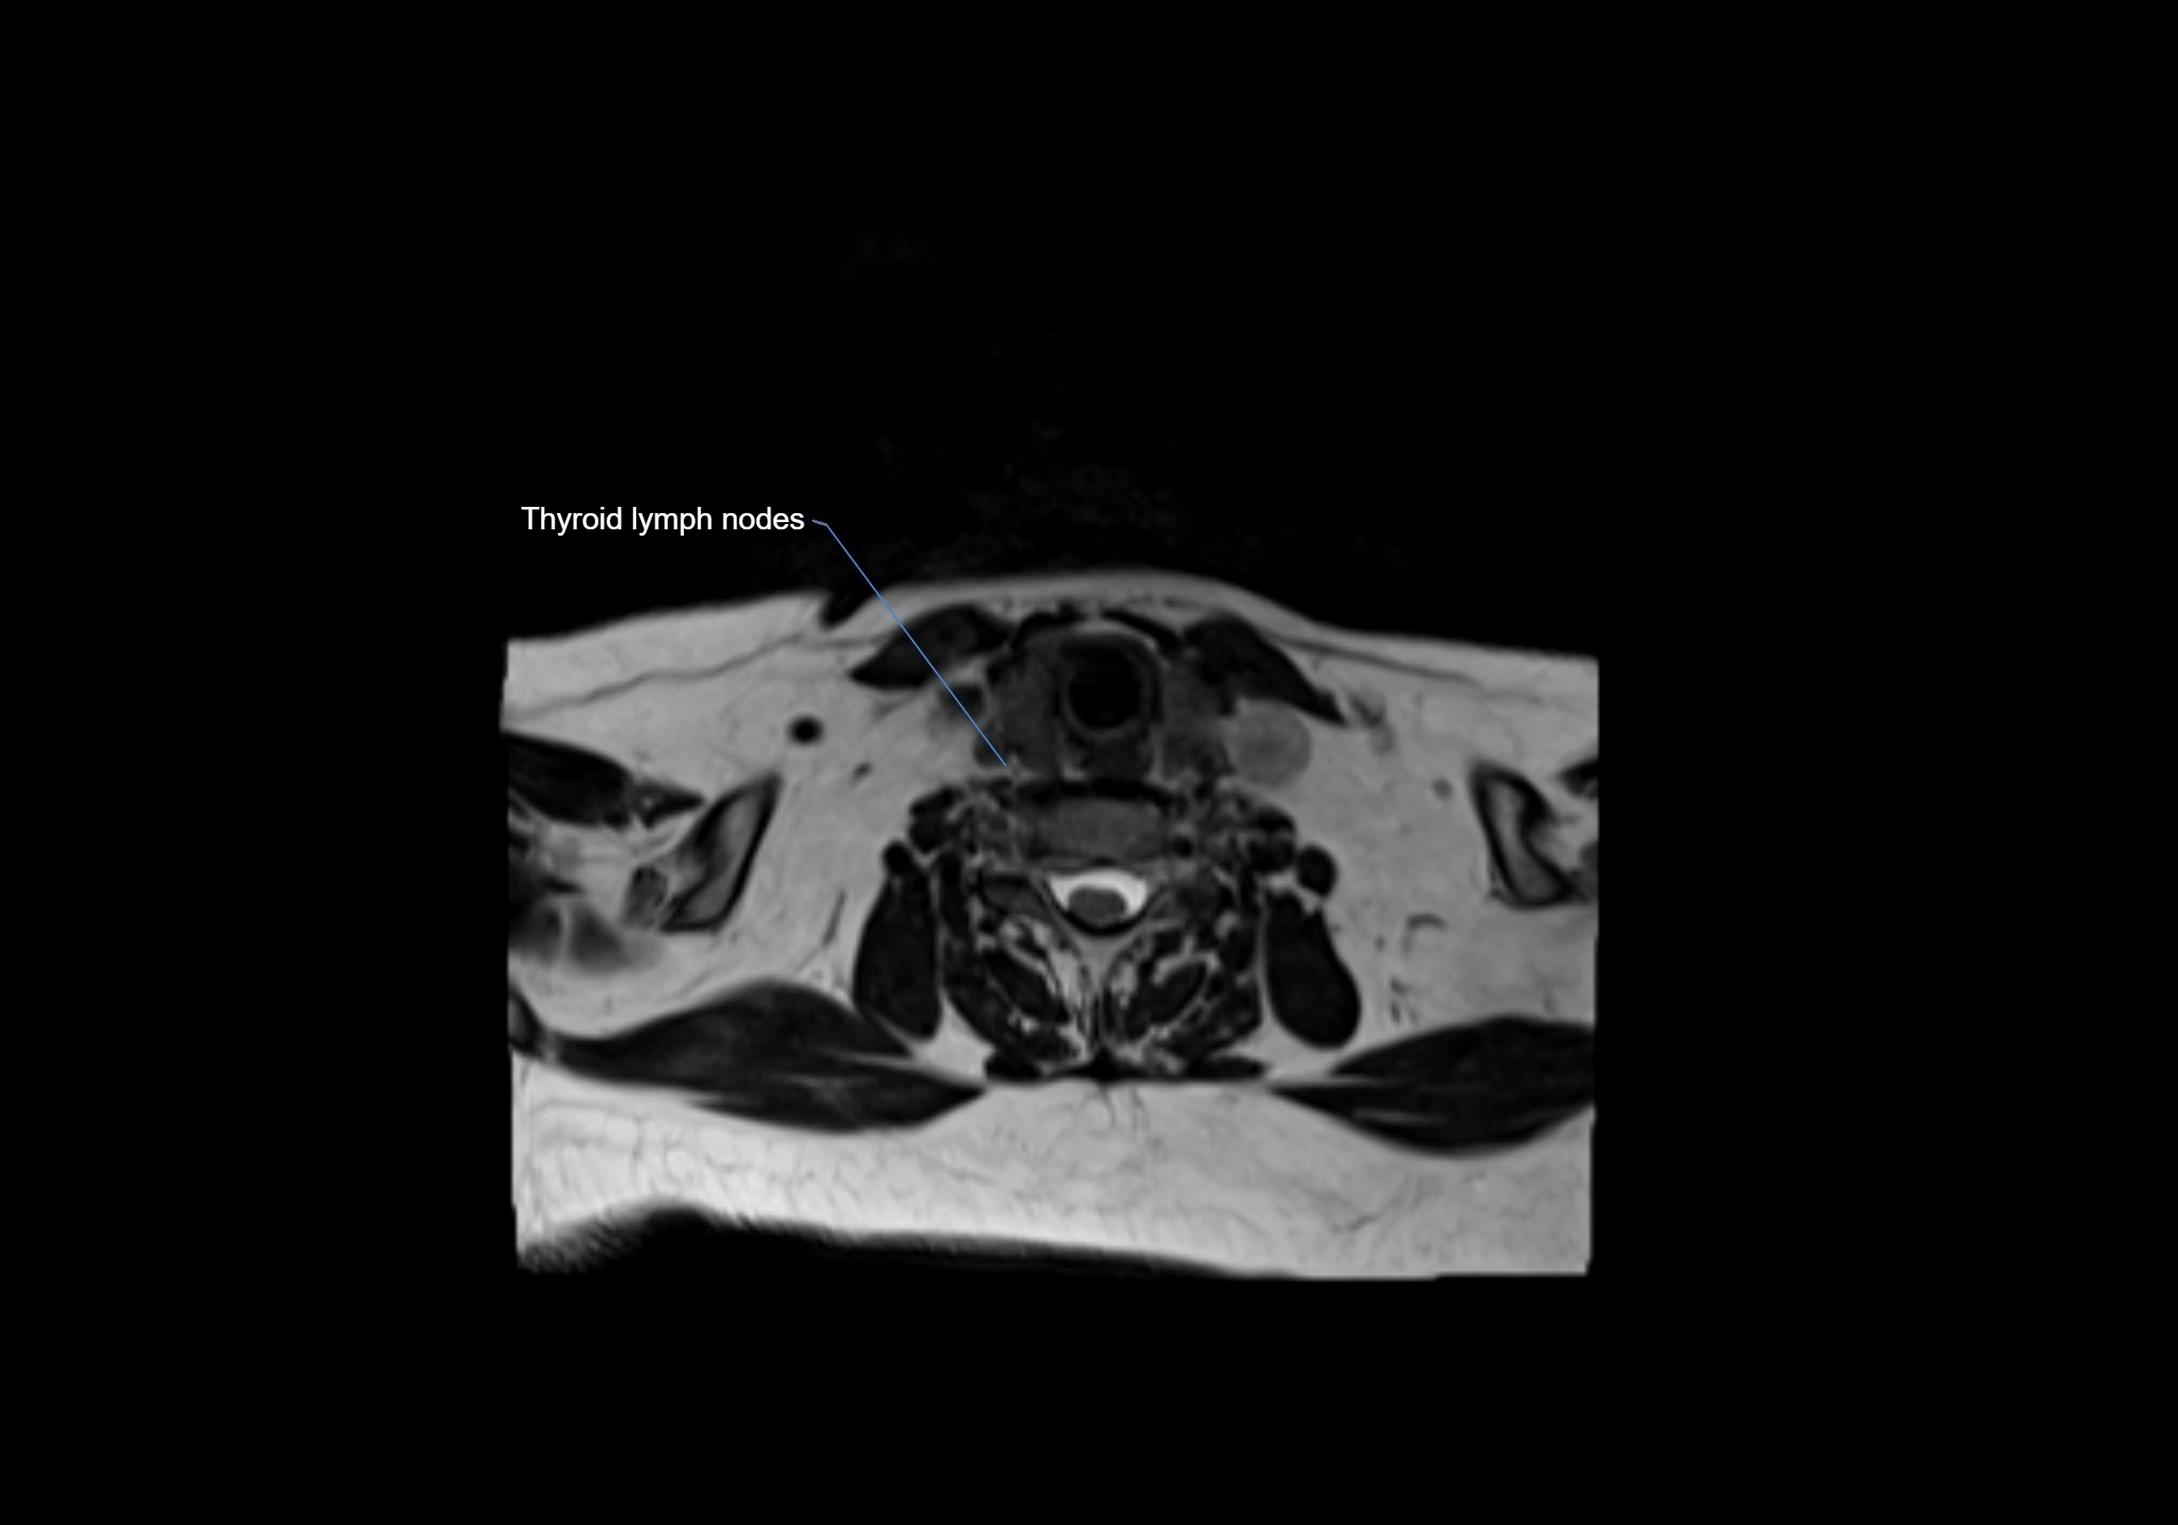

MRI Appearance

T1-weighted images:

• Normal accessory nodes appear as small, oval hypointense to intermediate signal structures within subcutaneous fat

• Surrounded by hyperintense fat, enhancing contrast for visualization

• Pathological nodes may appear enlarged or rounded, sometimes with cortical thickening

T2-weighted images:

• Nodes show intermediate signal, with surrounding fat bright

• Useful for detecting edema, inflammation, or infiltration

• Fatty hilum may appear slightly hyperintense relative to cortex

MRI images

image